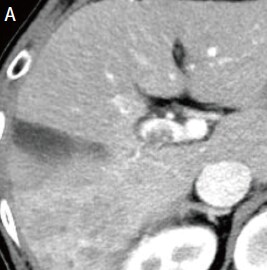

Administration of 800 mg/day sorafenib was then initiated, but progressive disease was still found, so the treatment was switched to 160 mg/day regorafenib. Imaging then showed marked anti-tumor efficacy (complete response), but PIVKA-II was later found to increase again. It was difficult to identify the locus of recrudescence by contrast computed tomography (CT; Fig. 1C), so EOB-MRI was performed (Fig. 2).

Fig. 1. Contrast CT images, arterial phase

A: Before sorafenib administration. B: After sorafenib administration for 2 months, before regorafenib administration. C: After regorafenib administration for 5 months: Top: Approximately the same section as with EOB-MRI; bottom: section showing the maximum tumor contrast enhancement.